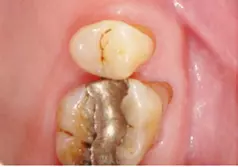

In der Praxis werden an Patienten zuweilen mit Messsonden diverse Größen ausprobiert, um eine entsprechende Empfehlung abzugeben [26]. Allerdings ist ihr Wert umstritten. Eine korrekt angepasste Interdentalraumbürste sollte den kompletten Interdentalraum reinigen und mit „mittlerem“ Druck ein- und auszuführen sein. Wenn sie zu dünn ist, hat sie eine zu geringe Reinigungswirkung; ist sie hingegen zu dick, besteht Traumatisierungsgefahr. Abbildung 2 zeigt die Einprobe und Auswahl am Beispiel des Interdentalraums 41/42.